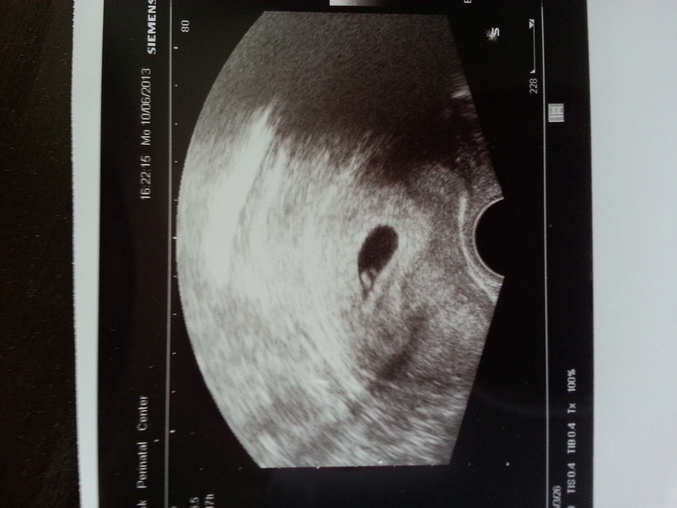

Счастливая!!!

Ну фото моего узи здесь есть) но не видно там вроде двоих)) хотя там вообще не понять кого видно!!

Бусинку твою я видела. На таком сроке однояйцевых не видно еще. Только к 12 неделям видать. Так, что еще есть время.